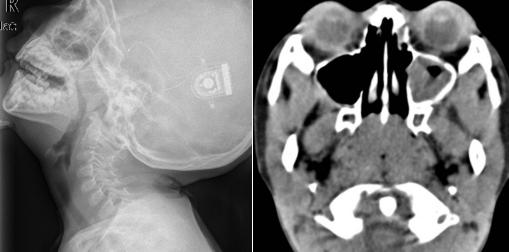

腺样体,也称为咽扁桃体或增殖体,位于鼻咽的顶部和咽后壁。它们属于淋巴组织,表面呈橙花瓣状。腺样体和扁桃体一样,出生后随年龄增长逐渐长大,2-6岁增殖旺盛,10岁后逐渐萎缩。腺样体由于炎症的反复刺激而病理性增生,导致鼻塞、张口呼吸的症状,尤其在夜间加重,出现睡眠打鼾、坐立不安。孩子经常会不时翻身,仰卧时更明显。严重时可能会出现呼吸暂停。随着口呼吸时间的延长,儿童上颌骨变长,牙列不全,上门牙外露,嘴唇变厚,甚至形成“腺样体脸”。本病多见于儿童,常与慢性扁桃体炎和扁桃体肥大并存。

腺样体肥大的危害这么大,我们该怎么处理?对于腺样体肥大,betway在线登陆耳鼻喉科采用低温等离子手术治疗腺样体肥大。低温等离子射频技术是一种微创疗法,特别适合老年人和儿童。低温等离子微创技术的治疗原理是利用低温等离子射频的能量,在40度左右的低温下消融腺样体病变组织,从而恢复咽腔的正常通气。此外,该技术通过内镜治疗可将病变组织放大数倍,手术视野更清晰,操作更简单准确,保证了手术的安全性,降低了风险。